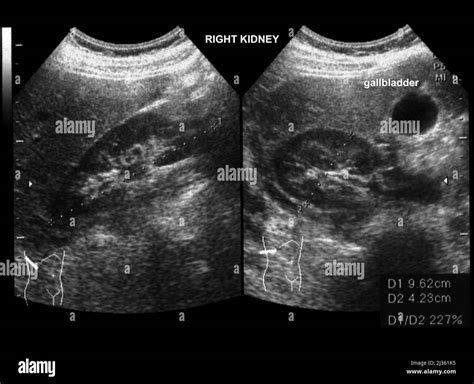

The term Normal Ultrasound Of Kidneys is standardized by medical imaging professionals. During the procedure, the sonographer maneuvers a transducer over your abdomen and back, capturing images from multiple angles. The following table summarizes what clinicians identify as normal characteristics compared to potential abnormal findings.

Parameter Expected Normal Finding Potential Abnormal Finding

Kidney Size Typically 9–12 cm in length Small/shrunken (chronic disease) or enlarged

Echogenicity Less than or equal to the liver/spleen Increased (suggests parenchymal disease)

Calyceal System No dilation or collection of fluid Hydronephrosis (dilation/obstruction)

Renal Outline Smooth, regular borders Irregular, lobulated, or scarred

Fluid Presence None, unless simple benign cysts Complex masses or stones (calculi)

After the radiologist interprets the images, they issue a report. If the report highlights a Normal Ultrasound Of Kidneys, it is a significant indicator that there are no major obstructive or structural pathologies present at that moment. However, medical results should always be contextualized. For example, some people have anatomical variations, such as a "horseshoe kidney" or a duplex collecting system, which are congenital differences that are not necessarily "diseased" but are considered variations of normal.